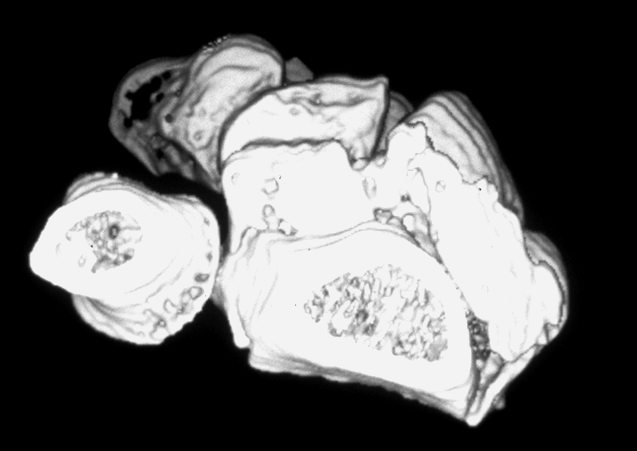

Case 3 CT